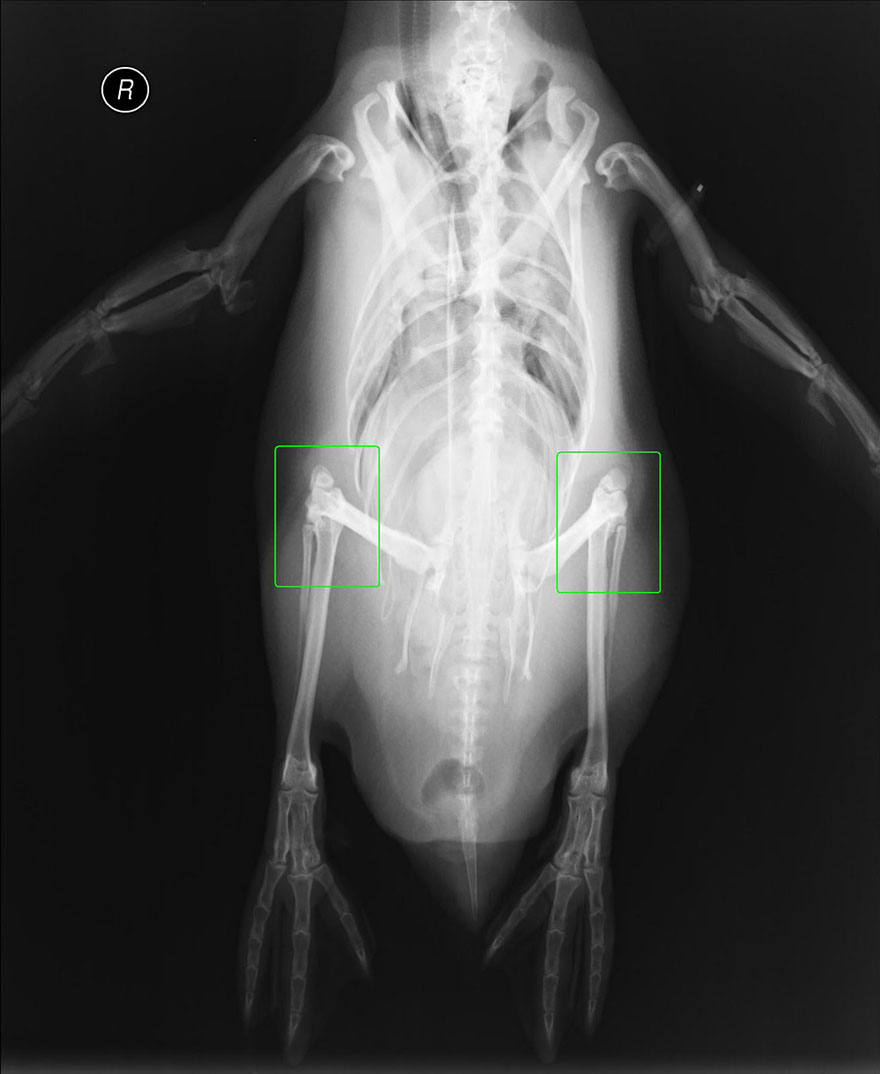

ROMA – Anche i pinguini hanno le ginocchia. Questi adorabili animali, hanno le stesse ossa delle gambe presenti nella maggior parte dei vertebrati bipedi. A differenza però degli altri vertebrati, parte di queste ossa sono coperte dalle piume.